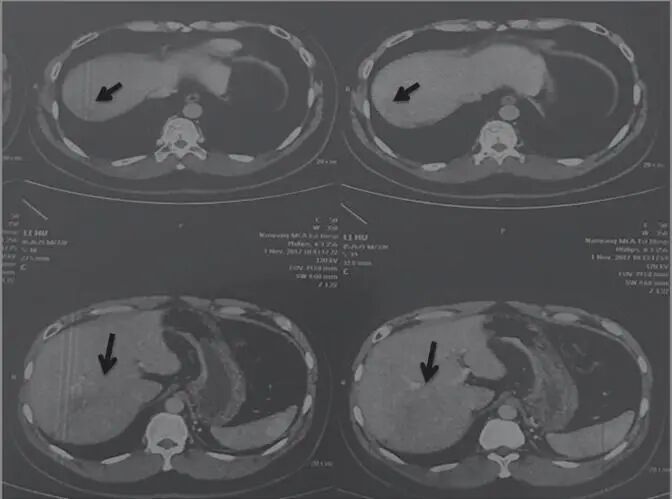

2017年11月18日,患者自述喝酒、熬夜,導(dǎo)致轉(zhuǎn)氨酶輕度升高。囑患者仍用原方服用3月余。2018年3月30日,檢查示肝占位病變,考慮肝癌。腫瘤大小為53.4mm×41.8mm(圖3)。

圖3 舒達(dá)少陽(yáng)防治腫瘤驗(yàn)案2018年3月30日CT結(jié)果

治療回顧:男性,32歲,乙肝病史10年,2016年5月7日,檢查示肝右葉巨大占位性病變,15cm×13.2cm;經(jīng)用舒少陽(yáng)、散結(jié)聚、健脾胃、寧心神的方法治療,2018年3月30日復(fù)查示肝頂部積水,肝右后葉可見不規(guī)則腫塊,邊緣模糊,最大5.34cm×4.18cm,純中藥治療后腫塊體積減小,帶瘤生存,生活質(zhì)量好。